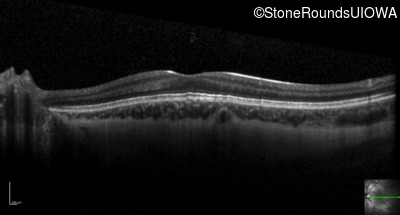

Optical Coherence Tomography - Left - 20/160 +1

Exemplar / OCT Stack

OCT Stack